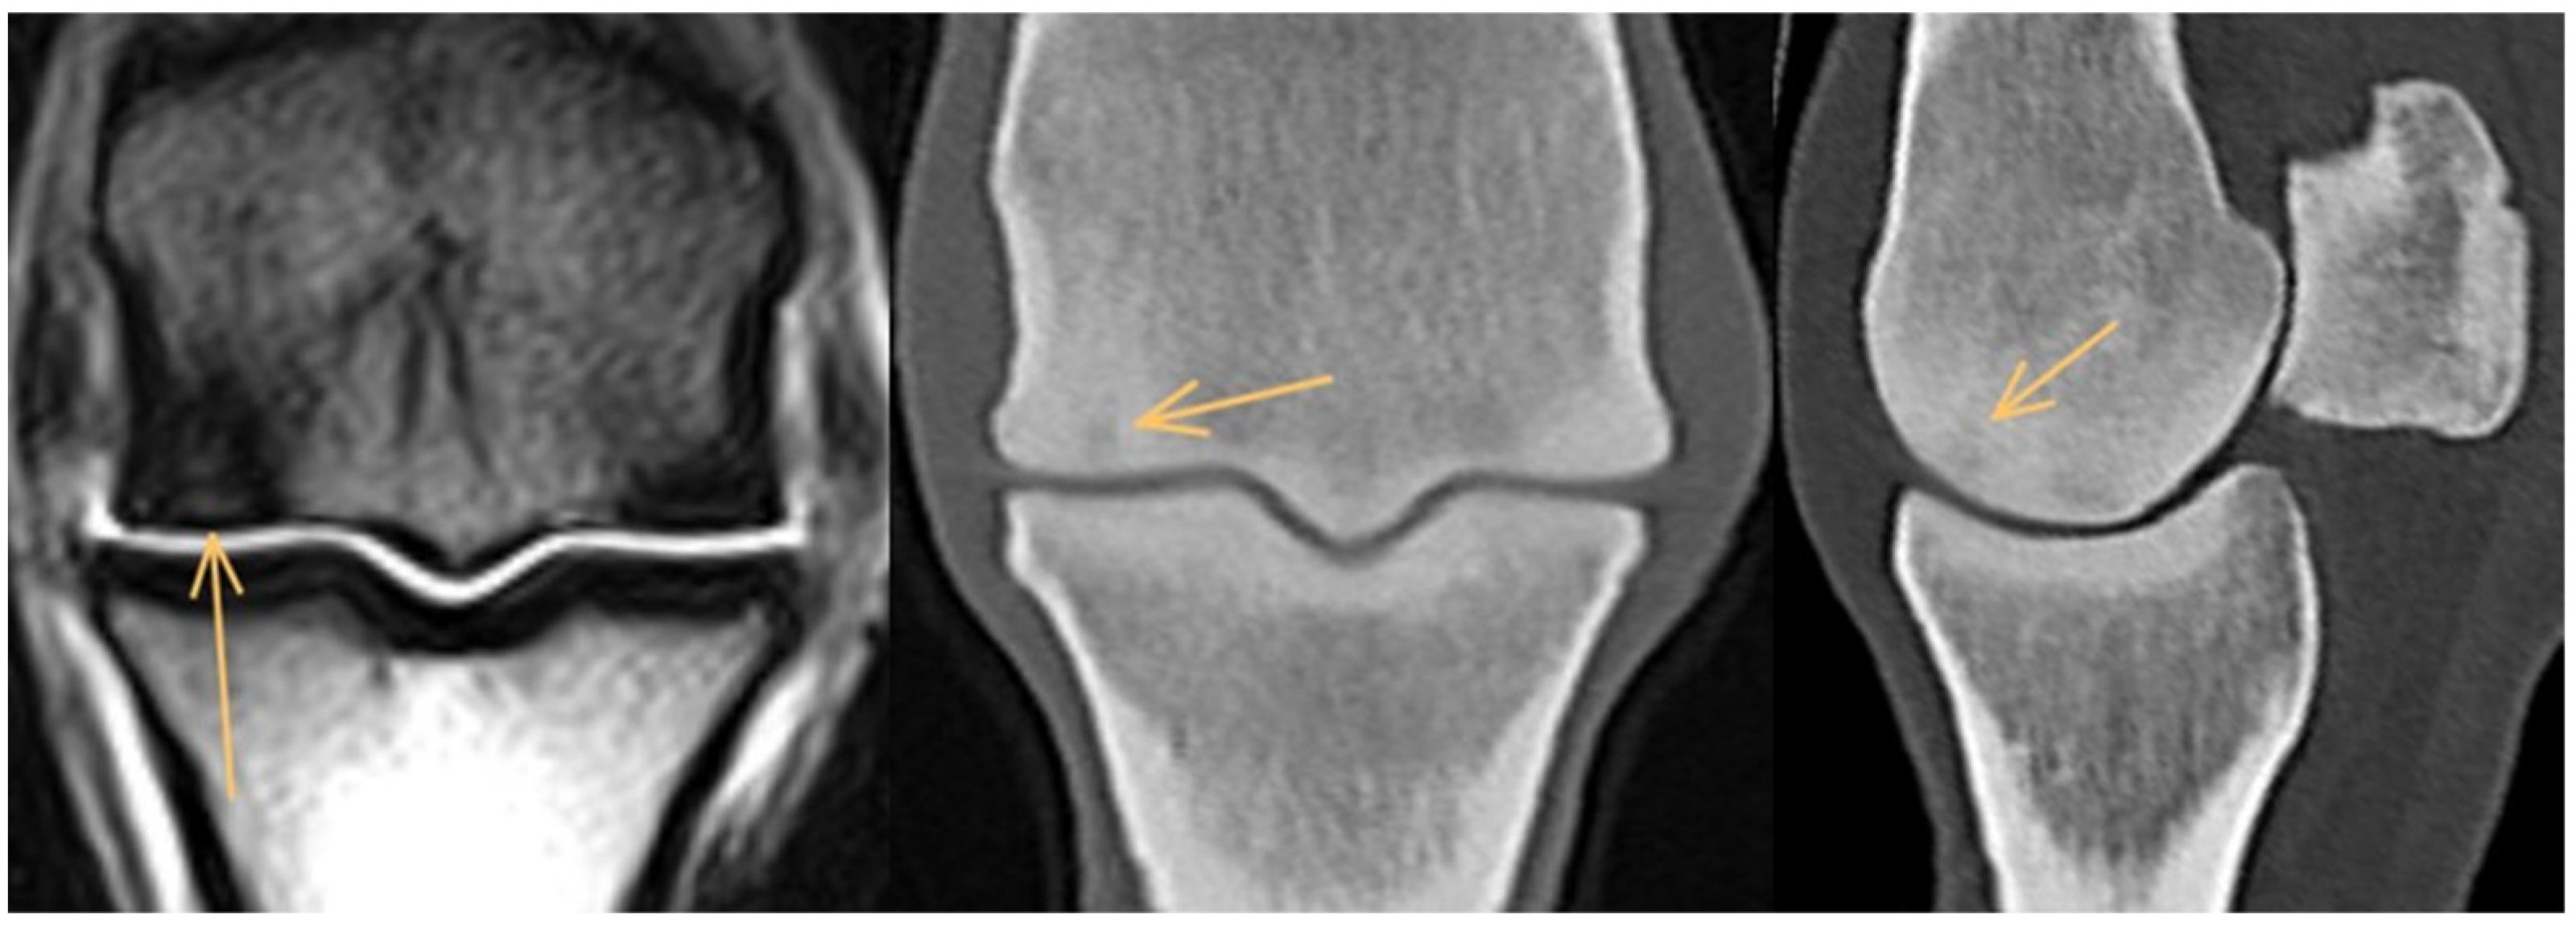

3.2. Proximal Phalanx